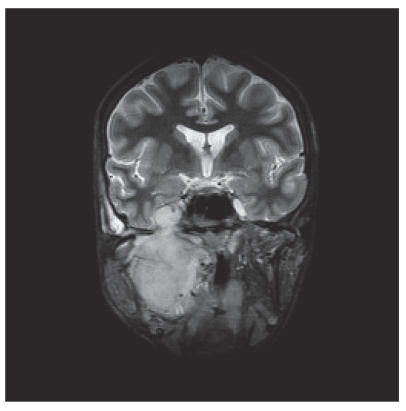

CT and MRI showed a large tumor in the right infratemporal fossa with intracranial extension through the foramen ovale to the cavernous sinus and growth in the posterior wall of the maxillary sinus and destruction of the ascending part of the mandible (Figure 2).

Figure 2.

MRI (coronal view) showed the tumor in the right infratemporal fossa with intracranial extension and invasion of the maxillary sinus and mandible.